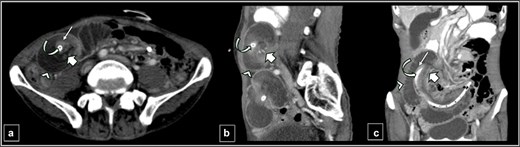

Six weeks later, the patient presented with acute abdominal pain and vomiting. A physical examination revealed mild abdominal distension with tenderness upon palpation. Given the patient’s medical history, the clinical presentation raised concerns of a possible mechanical obstruction. A contrast-enhanced computed tomography (CT) scan of the abdomen revealed intussusception at the site of the feeding jejunostomy, with a bowel segment telescoping into itself, leading to obstruction (Fig. 1).

Contrast-enhanced CT abdomen images of axial (a), sagittal (b), and coronal (c) sections showing the jejunojejunal intussusception with a target sign. The structures from outer to inner: grossly dilated intussuscipiens-distal jejunal loop (arrow head), the intussusceptum-proximal jejunal loop (long thin arrow), proximal jejunal mesenteric fat and the vessels (short thick arrow) within the intussuscipiens, and the feeding jejunostomy tube (curved arrow) within the intussusceptum.